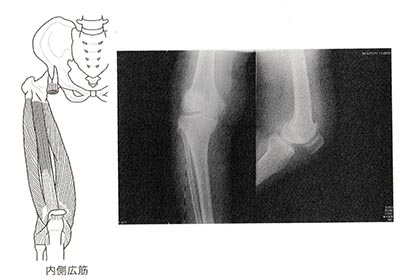

「関節内水腫はなく、レントゲンで内側関節裂隙の狭小化を認め、変形性膝関節症と診断がつきました。内側広筋にプラセンタ2アンプルをトリガーポイント注射し、膝のテーピングも併用しました。同時に漢方薬の防巳黄耆湯も処方しました」

「変形性膝関節症は加齢によって膝軟骨磨り減り、関節裂隙が狭くなる病気です。ただし、1週間以内、あるいは1〜3ヵ月以内に膝を過度に使ったことによる内側広筋の硬結が原因になることもあります。内側広筋へのプラセンタのトリガーポイント注射で膝関節通が短期間で軽くなることもよくあります」